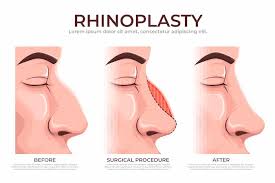

Rhinoplasty in Panna Rhinoplasty in Panna is a specialized aesthetic procedure designed to reshape and refine the nose for improved facial harmony and function. Moreover, increasing awareness of facial...